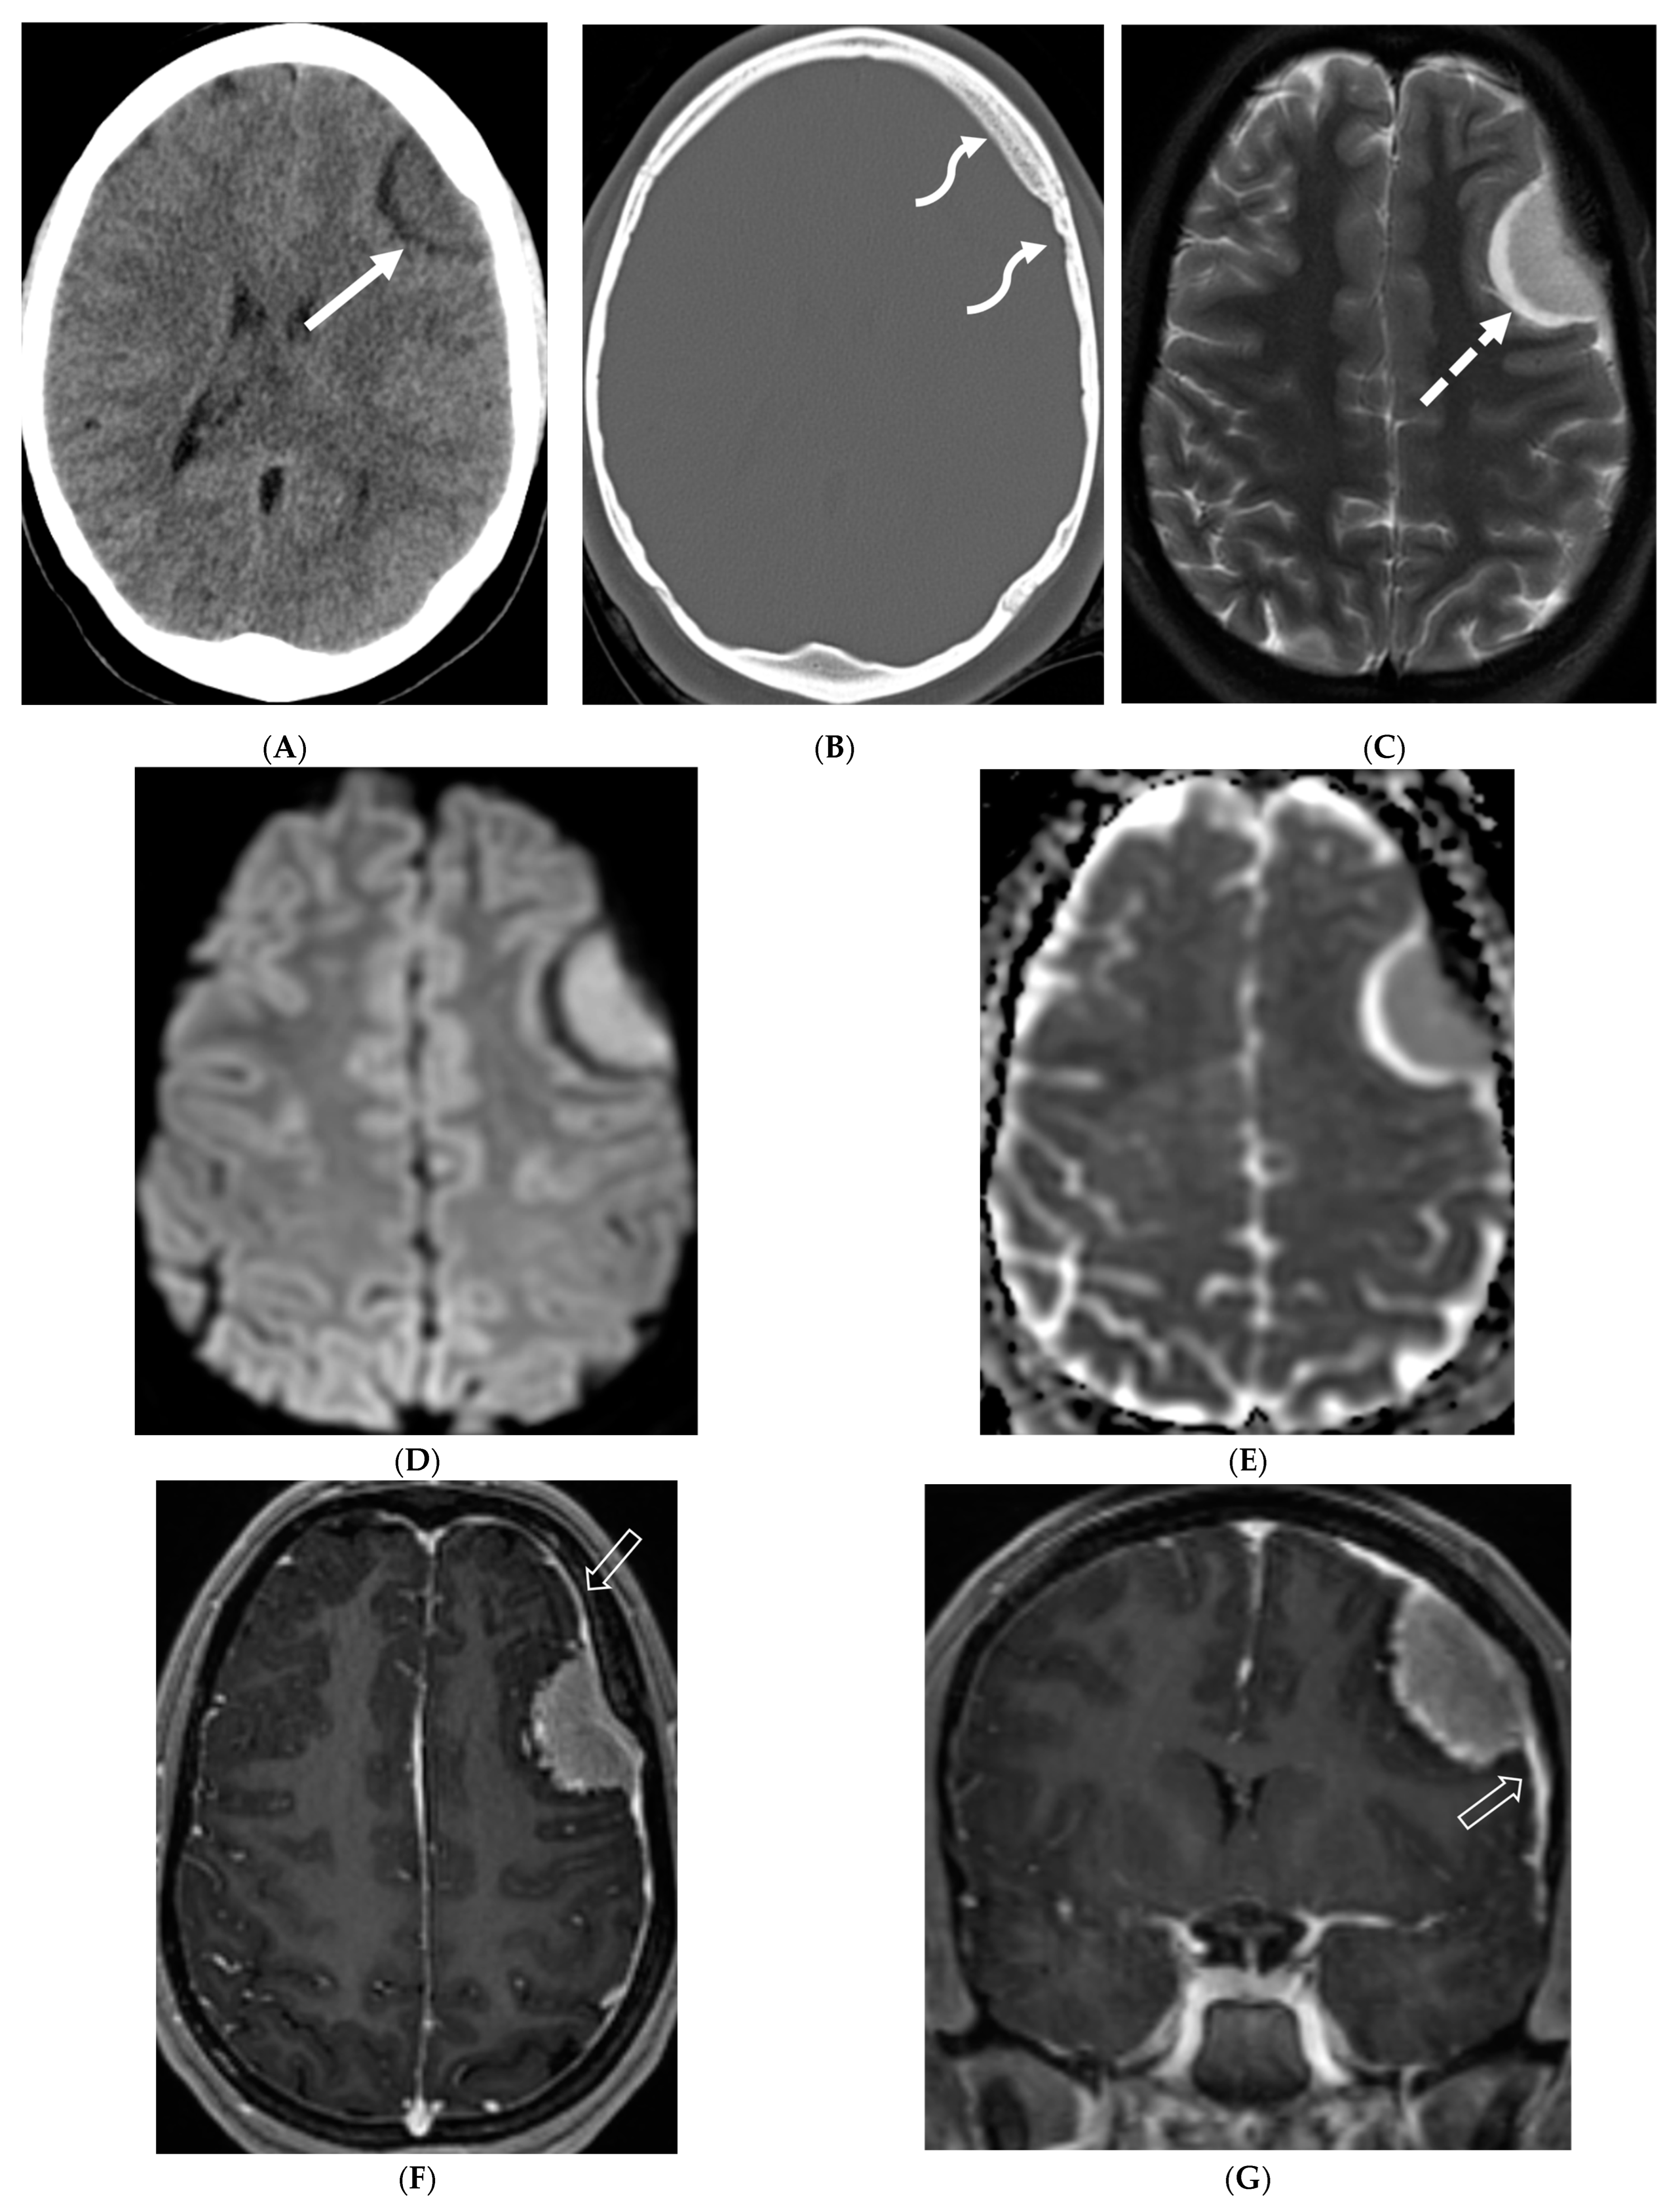

Figure 6.

Axial FLAIR (A), Axial T2 orbits (B), Axial T1 orbits post contrast (C) and axial T1 post contrast (D): 13-year-old female with headache and blurred vision. Abnormal FLAIR hyperintensity involving the left parieto-occipital periventricular white matter (arrow), and bilateral cerebellar hemispheres. Bilateral papilledema (black arrow) and edematous left optic nerve (dashed arrow). Peripheral optic nerves/optic sheath enhancement in the posterior aspect (curved arrows). Demyelination, infectious and metastatic processes were considered. MRI brain 6 months later with persistent symptoms demonstrates patchy and asymmetric pachymeningeal and leptomeningeal enhancement (open arrows). Pathology: Diffuse Leptomeningeal Glioneuronal Tumor.